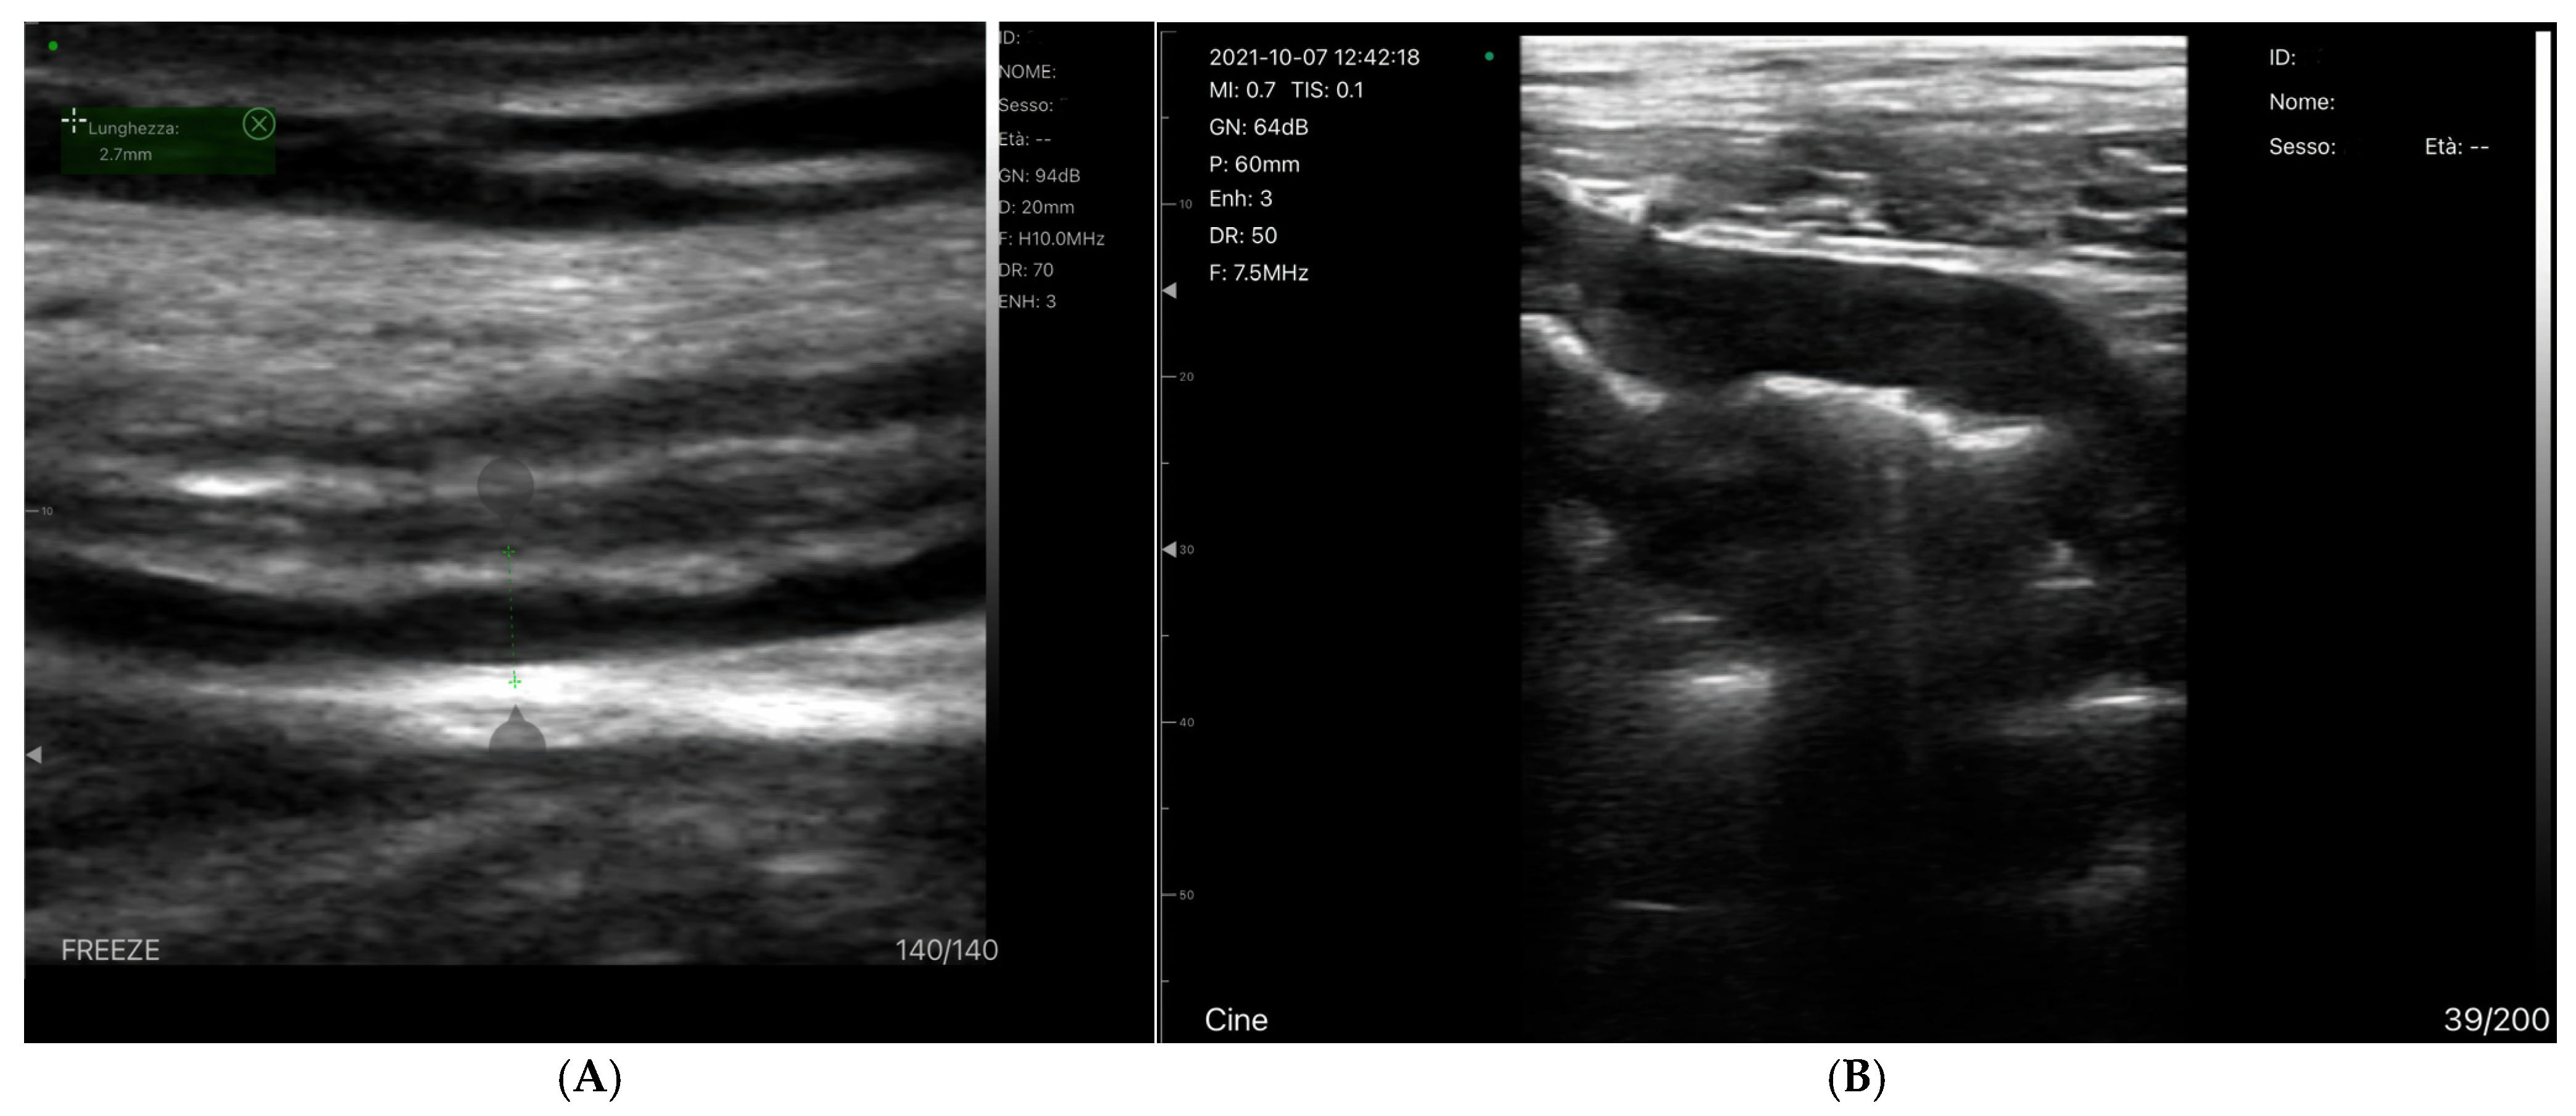

Bowel-Wall Thickening

Venous Congestion